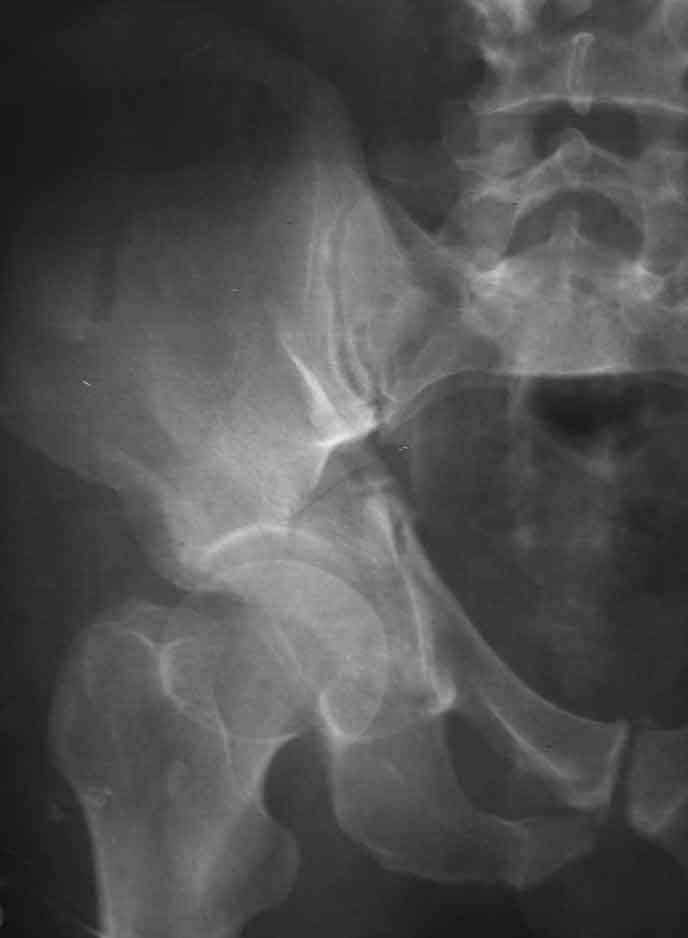

Dear Friends This is a 57 y old male.

Your input is welcome as to the classification of this fratcure, as well as the proposed management.

Dear Sir it looks quite difficult classify this fracture because the iliac view is not so clear.

In my opinion it is a column fracture because the obturator foramen is interrupted. There is a fracture of the posterior wall. If we assume the ap view as an iliac view it could be an anterior comun fracture plus posterior wall. It is difficult also to judge the head of the femur.

From the x rays it appears like a bicolumnar fracture with iliac extension (AO C1).

I am sending another iliac view, and a marked version of the AP I already sent. In this AP, the

proximal part of the greater sciatic notch as well as the distal parts of the ilioischial and iliopubic lines are marked with a grey interrupted line. A white interrupted line marks what could be an exit through the obturator foramen, or so I assume.